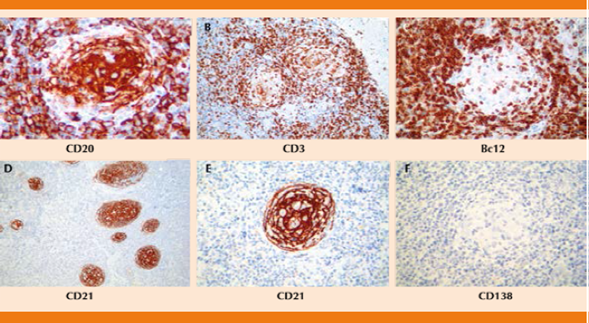

Reporte de inmunohistoquímica: CD 68: negativo, CD 3: positivo reactivo, CD 20: positivo reactivo, CD 138: negativo, BcL-2: negativo en centro germinal, BcL-6: positivo focal, CD 21: positivo en el centro germinal (Figura 4).

Figura 4 Reacciones de inmunohistoquímica que muestran positividad para CD20 en linfocitos B del centro germinal (A), para CD3 en linfocitos del manto y de la zona interfolicular (B), negatividad para bcl-2 en la zona del centro germinal (C) y positividad para CD21 en células dendríticas foliculares de los centros germinales (D, E). No se encontraron células plasmáticas, evidenciadas con esta reacción para CD138 que resultó negativa (F).